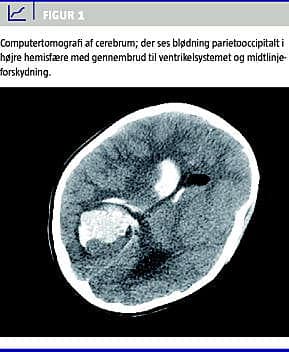

Ved ankomsten til hospitalet var patienten tiltagende bevidsthedspåvirket, Glasgow Coma Scale 6 (ingen øjenåbning, intet verbalt respons, men afværgereaktion - motorisk meget rodende), ikke nakke-ryg-stiv, hun havde fortsat spontan respiration, men var afebril. Der var pupildifference; den højre pupil var stor, dilateret og ikke lysreagerende. Pigen blev straks sederet og intuberet, og på mistanke om cerebral katastrofe blev der foretaget akut computertomografi (CT) af cerebrum. Denne viste blødning parietooccipitalt i højre hemisfære med gennembrud til ventrikelsystemet og en midtlinjeforskydning på knap 2 cm (Figur 1 ).